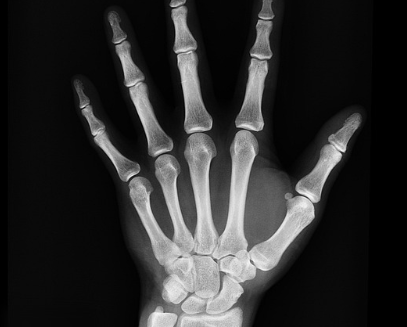

다발성골수종은 비정상적인 형질세포가 골수에서 증식하여 정상적인 혈액 세포의 생산을 방해하는 질환입니다. 이로 인해 면역력 저하, 빈혈, 뼈 통증 등의 증상이 나타납니다. 다발성골수종 주요 증상에는 특히 척추, 갈비뼈, 골반에서 통증이 발생할 수 있으며, 골절의 위험이 증가합니다. 두 번째 증상에는 적혈구 수가 감소하여 피로감, 무기력함, 숨 가쁨 등의 증상이 나타날 수 있습니다. 세 번째 증상에는 신장 기능 저하로 인한 부종, 소변 변화, 고혈압 등이 발생할 수 있습니다. 네 번째 증상에는 비정상적인 형질세포의 증식으로 인해 면역 체계가 약화되어 감염에 대한 저항력이 떨어지고, 잦은 감염이 발생할 수 있습니다. 마지막 증상으로는 뼈에서 칼슘이 방출되어 혈중 칼슘 농도가 증가할 수 있으며, 이는 구토, 혼란, 탈수 등의 증상을 유발할 수 있습니다.